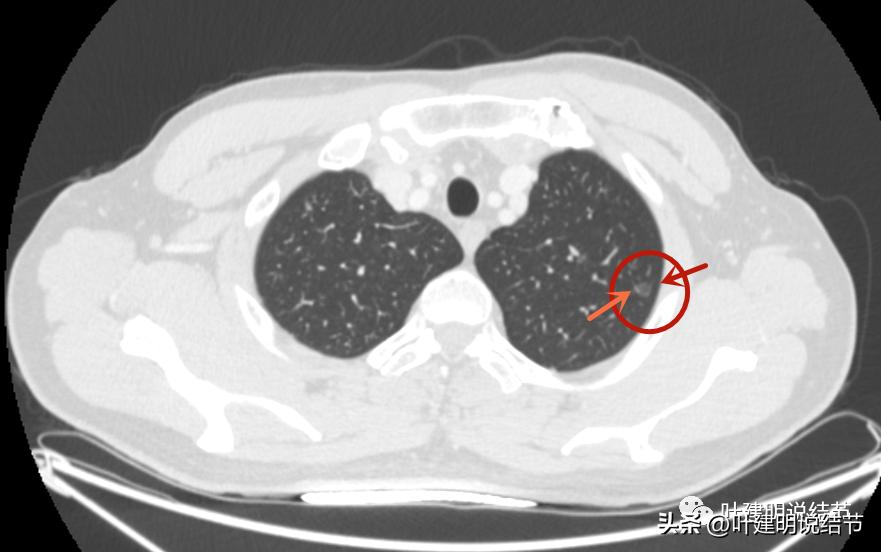

病灶2:右上叶结节

右上有微小磨玻璃结节,见血管穿行,整体密度也不高,但似乎比左侧的略高点。

病灶轮廓较清。

这两处结节均考虑是肿瘤范畴的,因为轮廓清,磨玻璃密度,并有血管穿行。但整体均还上,密度还很低,尤其左侧的密度更低。这样密度极低的磨玻璃结节,它周围的血管贴边并不似因为肿瘤生长需要富血供,从而吸引了新生血管过来,或周围血管发出分支来供血,而是“碰巧”有血管刚好经过的可能性更大些,且淡磨玻璃密度的结节基本不具有侵袭性,不至于侵犯或影响血管从而带来危险。如果一定要来预估一下病理会是什么,大概左侧以不典型增生可能性大,不能除外原位癌;右侧稍倾向原位癌,但也可能是不典型增生或肺泡上皮增生,至少近期风险低,能随访。

左侧磨玻璃结节红色圈起来的瘤肺边界清,有血管贴边,但整体密度低,没有实性成分,考虑仍是不典型增生或原位癌阶段,近期风险低,个人觉得最好先随访,因为可能很多年不变的,而且也可能再检出新的结节来。况且随访有进展再干预,效果也是一样的。右侧结节也是肿瘤范畴,但风险一样不高,建议同样半年到一年复查(其实1年也关系不大的)。意见供参考!